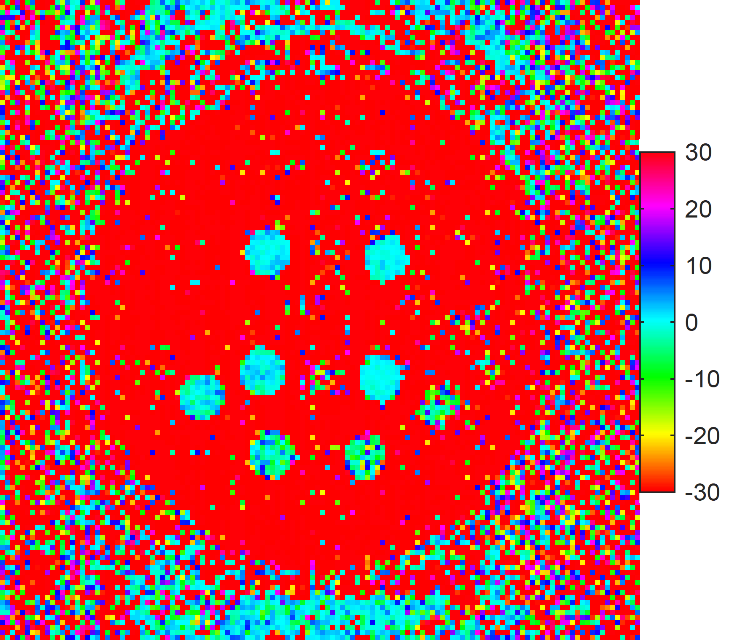

3.2.3 Computation of ηpsubscript𝜂𝑝\eta_{p}

The 𝜽𝒙GTsuperscriptsubscript𝜽𝒙𝐺𝑇\bm{\theta}_{\bm{x}}^{GT} and C𝒙,cGTsubscriptsuperscript𝐶𝐺𝑇𝒙𝑐C^{GT}_{\bm{x},c} were downsampled to |Ωx,D|=24×24superscriptΩ𝑥𝐷2424|\Omega^{x,D}|=24\times 24 by applying nearest-neighbor interpolation on each parameter map separately while undersampling patterns were generated specifically for Ωx,DsuperscriptΩ𝑥𝐷\Omega^{x,D}. Both the original and downsampled ground truth maps are shown in Figure 2. The ROI mask was obtained by applying the same downsampling operation to 𝜽𝒙GTsuperscriptsubscript𝜽𝒙𝐺𝑇\bm{\theta}_{\bm{x}}^{GT}, to the ROI mask used for Monte Carlo simulation. The ηpsubscript𝜂𝑝\eta_{p} for each voxel corresponding to voxels in the full-size map where nominal values are available was computed according to Equation 14.

Fig. 2: The ground truth maps acquired from a fully sampled acquisition of the Eurospin II TO5 phantom used in the Monte Carlo simulations are shown on the left, and downsampled version of the map for computation of TEUSQA is shown on the right.